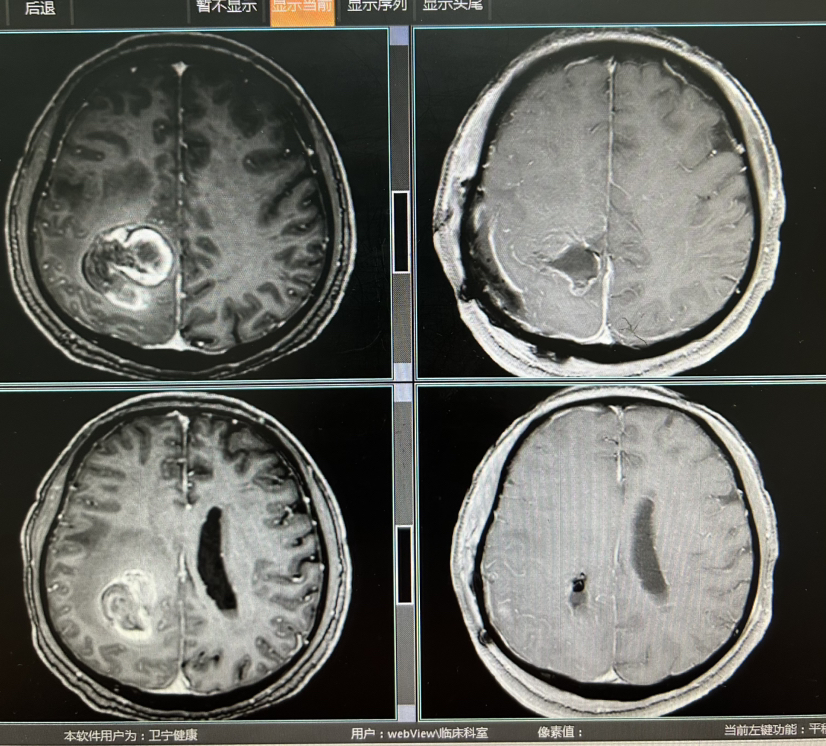

病例右侧功能区占位卒中一例镜下全切

脑血管-烟雾病脑血管-动脉瘤脑血管-动静脉畸形脑血管-硬脑膜动静脉瘘脑血管-海绵状血管瘤/畸形脑肿瘤-胶质瘤脑肿瘤-脑转移瘤脑肿瘤-脑膜瘤神经介入-其他卢云鹤 昨天15:51 27阅读 0评论 0点赞